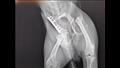

وكانت الأرجل الخلفية لـ "هوسون" مكسورة بسبب حادث السيارة، لذا كانت غير قادرة على المشي، وأعطاها أصحابها بعض الماء وأخذوها إلى طبيب بيطري حيث تم تشخيص حالتها بأنها تعاني من كسور متعددة في الحوض والساقين، ومع ذلك، لم يستطع الطبيب تفسير كيف تمكنت الكلبة من الزحف للخروج من قبرها والعودة إلى المنزل.

وخطفت قصة هوسون أنظار الملايين في كوريا الجنوبية، بما في ذلك جراح العظام البيطري الذي اتصل بأصحابها وعرض عليهم إجراء عملية جراحية لإعادة العظام إلى مكانها ومنع الإعاقة في المستقبل.